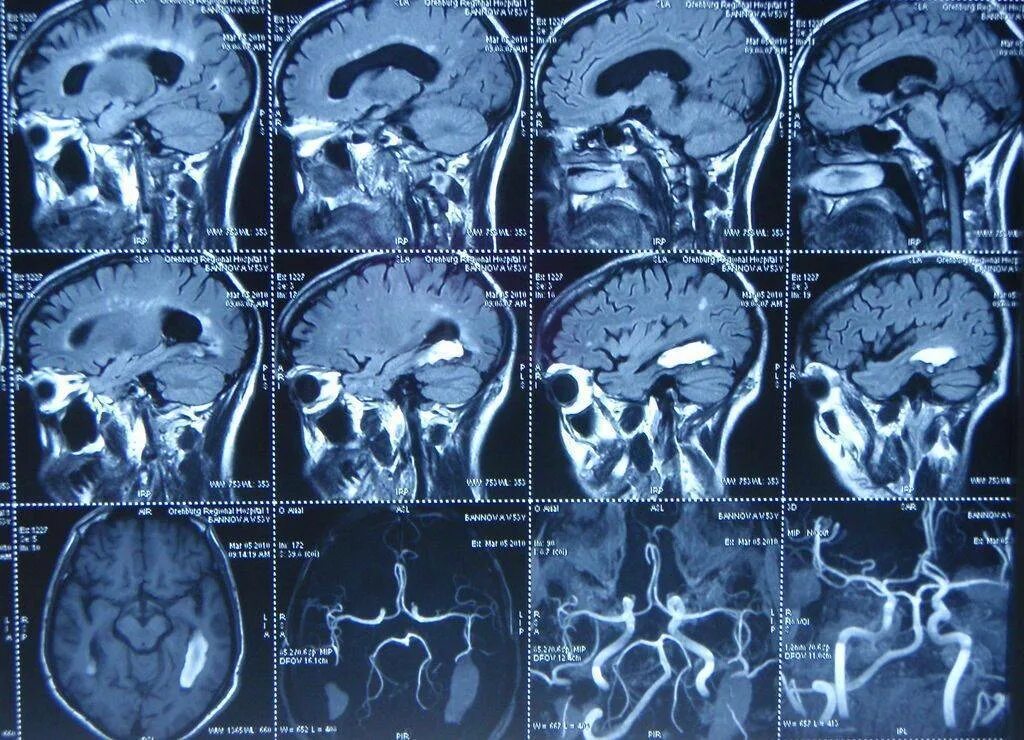

Что покажет мрт головного мозга с контрастом